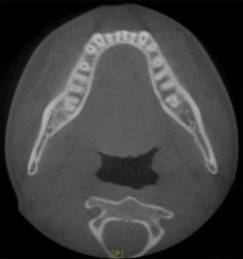

放射检查:一般包括X线头影测量片、曲面体层片和CBCT(锥束CT)。有时还包括其他放射检查,比如螺旋CT等。通过放射检查,医生可以看到骨骼及牙齿的形态、位置及发育状况,以及是否有牙体、根尖周、牙周疾病等,从而评估是否需要正畸治疗、进行何种治疗。

头影测量片(上)、曲面体层片(中)和锥束CT(下)